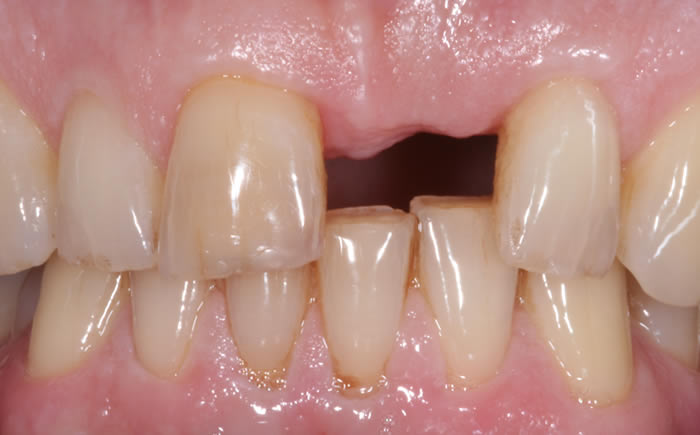

More front teeth replaced by dental implants

Case Three (4 images)